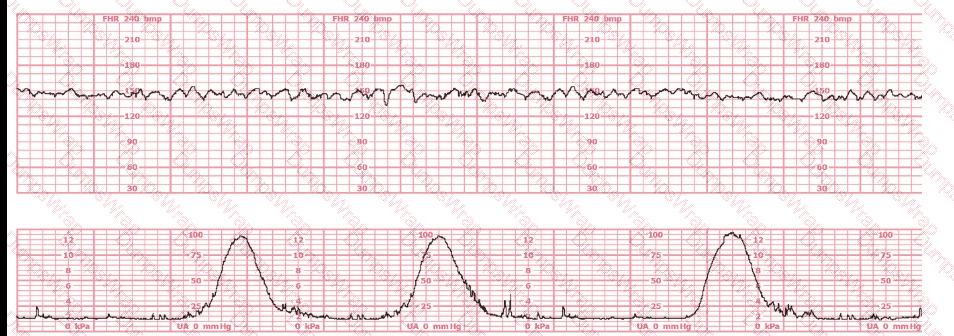

The tracing shown is from a woman at 28-weeks gestation in the post-anesthesia care unit (PACU) after an appendectomy. She is alert and awake. Based on this fetal heart rate pattern, the most appropriate intervention is:

Options:

Administer terbutaline

Continued monitoring

Perform cesarean birth

Answer:

BExplanation:

Comprehensive and Detailed Explanation From Exact Extract–Based NCC C-EFM References:

The fetal heart rate tracing shows:

Baseline around 140 bpm

Minimal variability

No accelerations

No decelerations

Regular uterine activity but not tachysystole

This pattern is Category II, but in the context of:

28-week gestation

Immediate postoperative status after anesthesia

Maternal alertness and stability

NCC and AWHONN emphasize that maternal sedation, post-anesthesia effects, medications, and physiologic stress commonly cause temporary minimal variability without acidemia, especially at preterm gestations where baseline variability is normally lower.

Key NCC principle:

Minimal variability in a stable mother without decelerations does NOT require emergent delivery.

Instead, the fetus should be observed as anesthesia effects wear off.

Why other answers are incorrect:

A. Terbutaline – No tachysystole and no recurrent decels are present.

C. Cesarean birth – No bradycardia, no late decels, no absent variability, and no Category III criteria.

Thus, appropriate management is B. Continued monitoring.